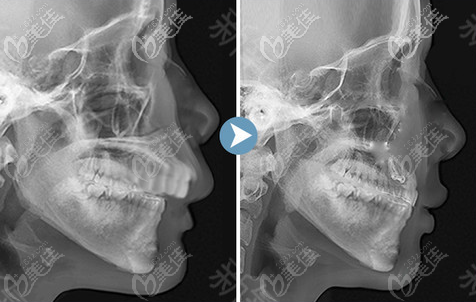

你好,上顎骨突出矯正價格在36800-68000元左右,具體價格根據(jù)自身面部基礎(chǔ)情況,以及選擇地區(qū)、醫(yī)院和醫(yī)生的不同,上顎骨突出矯正費(fèi)用也會有一定差異的。

上顎骨突出矯正手術(shù)屬于四級頜面整形手術(shù),具有一定的風(fēng)險,為了降低手術(shù)風(fēng)險,建議選大型正規(guī)具備四級頜面磨骨資質(zhì)的醫(yī)院和醫(yī)生進(jìn)行手術(shù)。